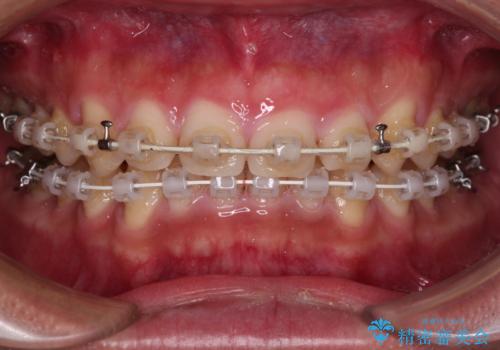

- 審美装置

- 1年5ヶ月

- 前歯の隙間と深い咬み合わせを改善したいとのことで来院された患者様です。

マウスピース矯正の自己管理が面倒とのことで、ワイヤー矯正により治療を行うこととしました。

奥歯の咬み合わせは理想的な状態であったため、ワイヤー矯正でもインビザラインでも比較的容易に対応可能でした。